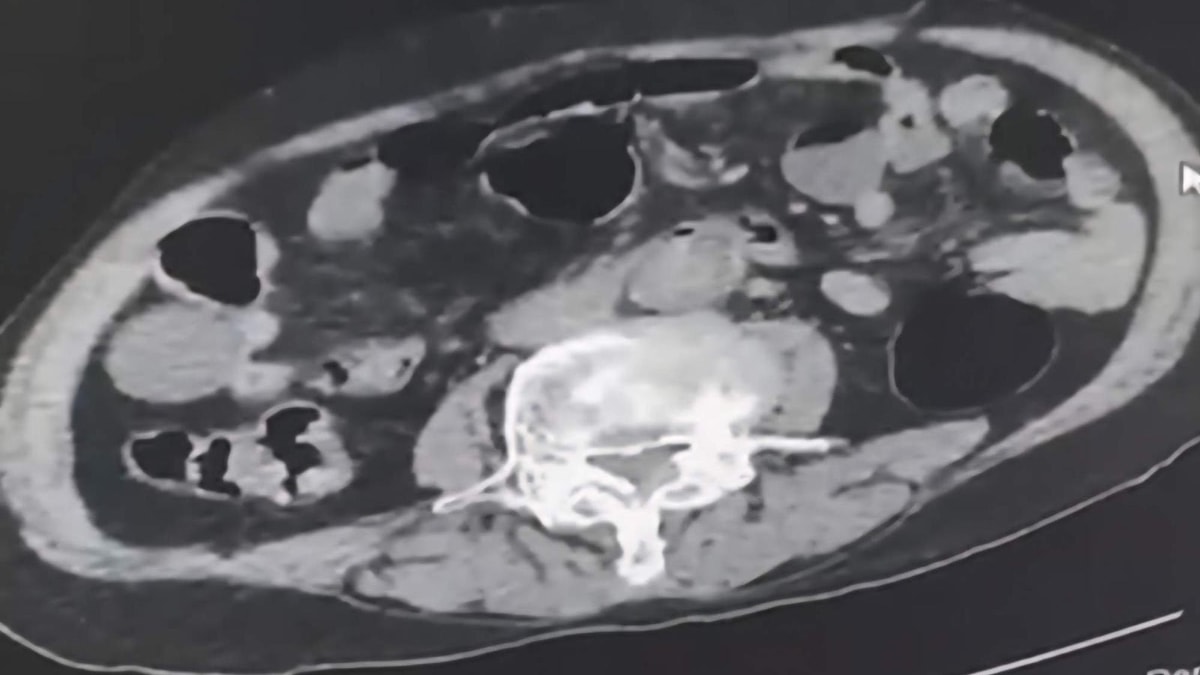

Gözaltına alınan şüpheliler üzerinde yapılan incelemelerde, yabancı uyruklu bir şüphelinin uyuşturucu maddeyi cinsel organında taşıdığı belirlendi.